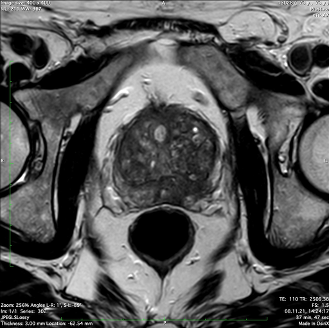

Cancer de la prostate

Examens d’imagerie médicale

IRM de la prostate pour la planification de la biopsie et la détection des cancers cliniquement significatifs.